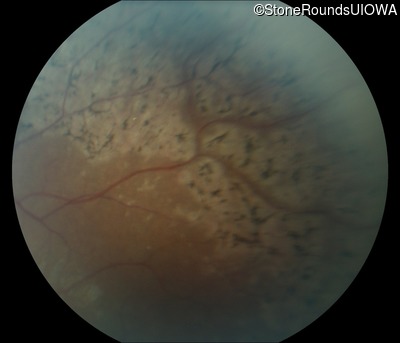

Fundus Photography - Right - 20/32 -1

Exemplar